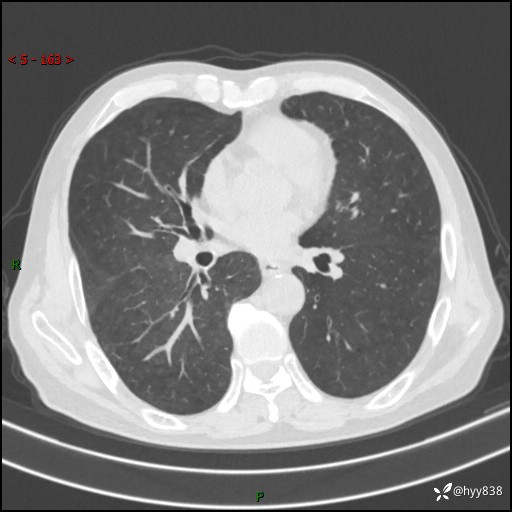

辅助检查:CT

胸部CT平扫